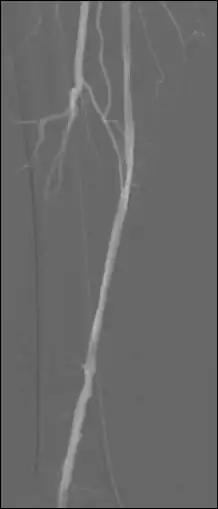

Open an image sequence in the 2D Viewer, and open the same sequence for a second time, so that the image sequence is displayed in two separate windows. Turn off synchronization by selecting 2D Viewer | Stack Syncronize | Off. Drag the icon of one window and drop it onto the image in the second window to call up the fusion functions and click the Subtraction button:

Pixel values displayed for subtracted images refer (correctly) to subtracted images with this option, although pixel shifting is not available. The Thick Slab module can be used to (effectively) integrate both mask images (before subtraction) and live images (before and following subtraction) so as to improve image SNR and to generate a vascular trace.